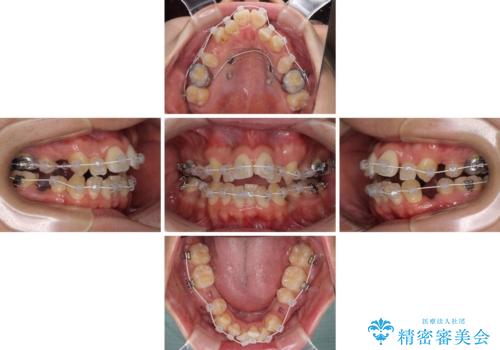

元の歯列が想像できないほど、きれいな歯列に整えることができました。

第二小臼歯抜歯の矯正治療は、治療期間が長引くことが多いですが、動きが非常に良く、予定の治療期間で終えることができました。